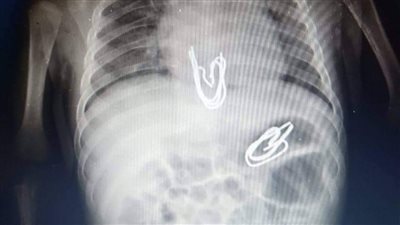

إنجاز طبي نادر بالإسكندرية.. فصل توأم طفيلي دون رأس عن رضيعة عمرها 4 أشهر

جراحة منظار بمستشفى الأطفال بالمنصورة تنقذ طفل 3 أشهر ابتلع

جراحة منظار بمستشفى الأطفال بالمنصورة تنقذ طفل 3 أشهر ابتلع "5 دبابيس"